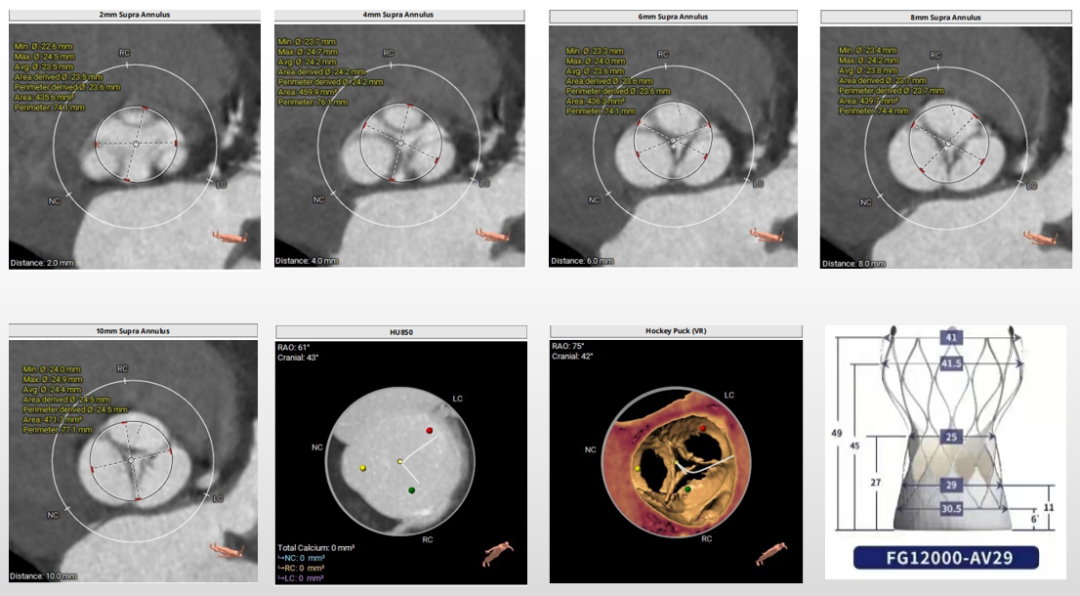

第三例术前评估

主动脉根部评估

三叶式主动脉瓣,瓣叶增厚,流出道呈敞口状,升主轻微扩张,左心室偏大,左冠窦瓣叶长度>瓣叶附着缘到冠脉开口的距离,术中有冠脉阻挡风险。

瓣环上解剖结构评估

无钙化,根据瓣环及瓣上情况,选AV29瓣膜。

外周血管及主动脉弓解剖

双侧髂主动脉轻度扭曲无钙化,双侧入路内径良好,选择右侧为主入路,左侧为辅入路。